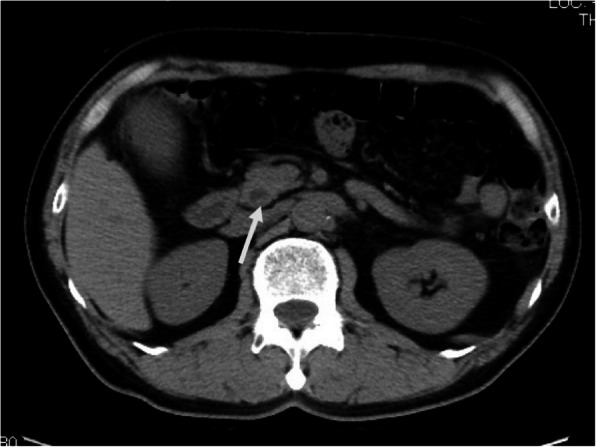

Abdominal contrast-enhanced computed tomography (CT) showed a slightly dilated CBD and a high-density spot in the DBD, suggesting a CBD stone (Fig. 1). Endoscopic ultrasonography demonstrated an elevated lesion on the DBD (Fig. 2). Permeation to the pancreatic parenchyma or to the outside of the bile duct wall was unclear. Endoscopic retrograde cholangiopancreatography (ERCP) revealed a circumferential stenosis 11.8 mm distal from the ampulla of Vater and a 5.1 × 6.5 mm irregularly shaped, elevated lesion on the DBD (Fig. 3). A double pig-tail catheter (7 Fr, 6 cm) was inserted in the bile duct. Brush cytology showed atypical ductal cells, indicating adenocarcinoma (AC) of the DBD.